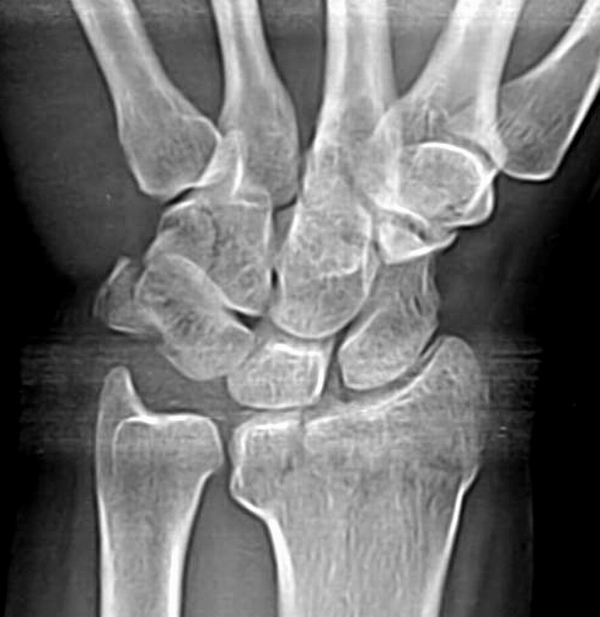

标题: 正位片

经验表明很多患者因腕部疼痛而在照像时不旋动腕关节而是旋动肘部(这时肘部必然伸直且用较大力),而且腕部紧张,这样就变成楼主的图像了.投照时注意纠正

此为腕关节标准正位片,图片来自\"眼睛\",各位可以对比一下与楼主图片有何不同